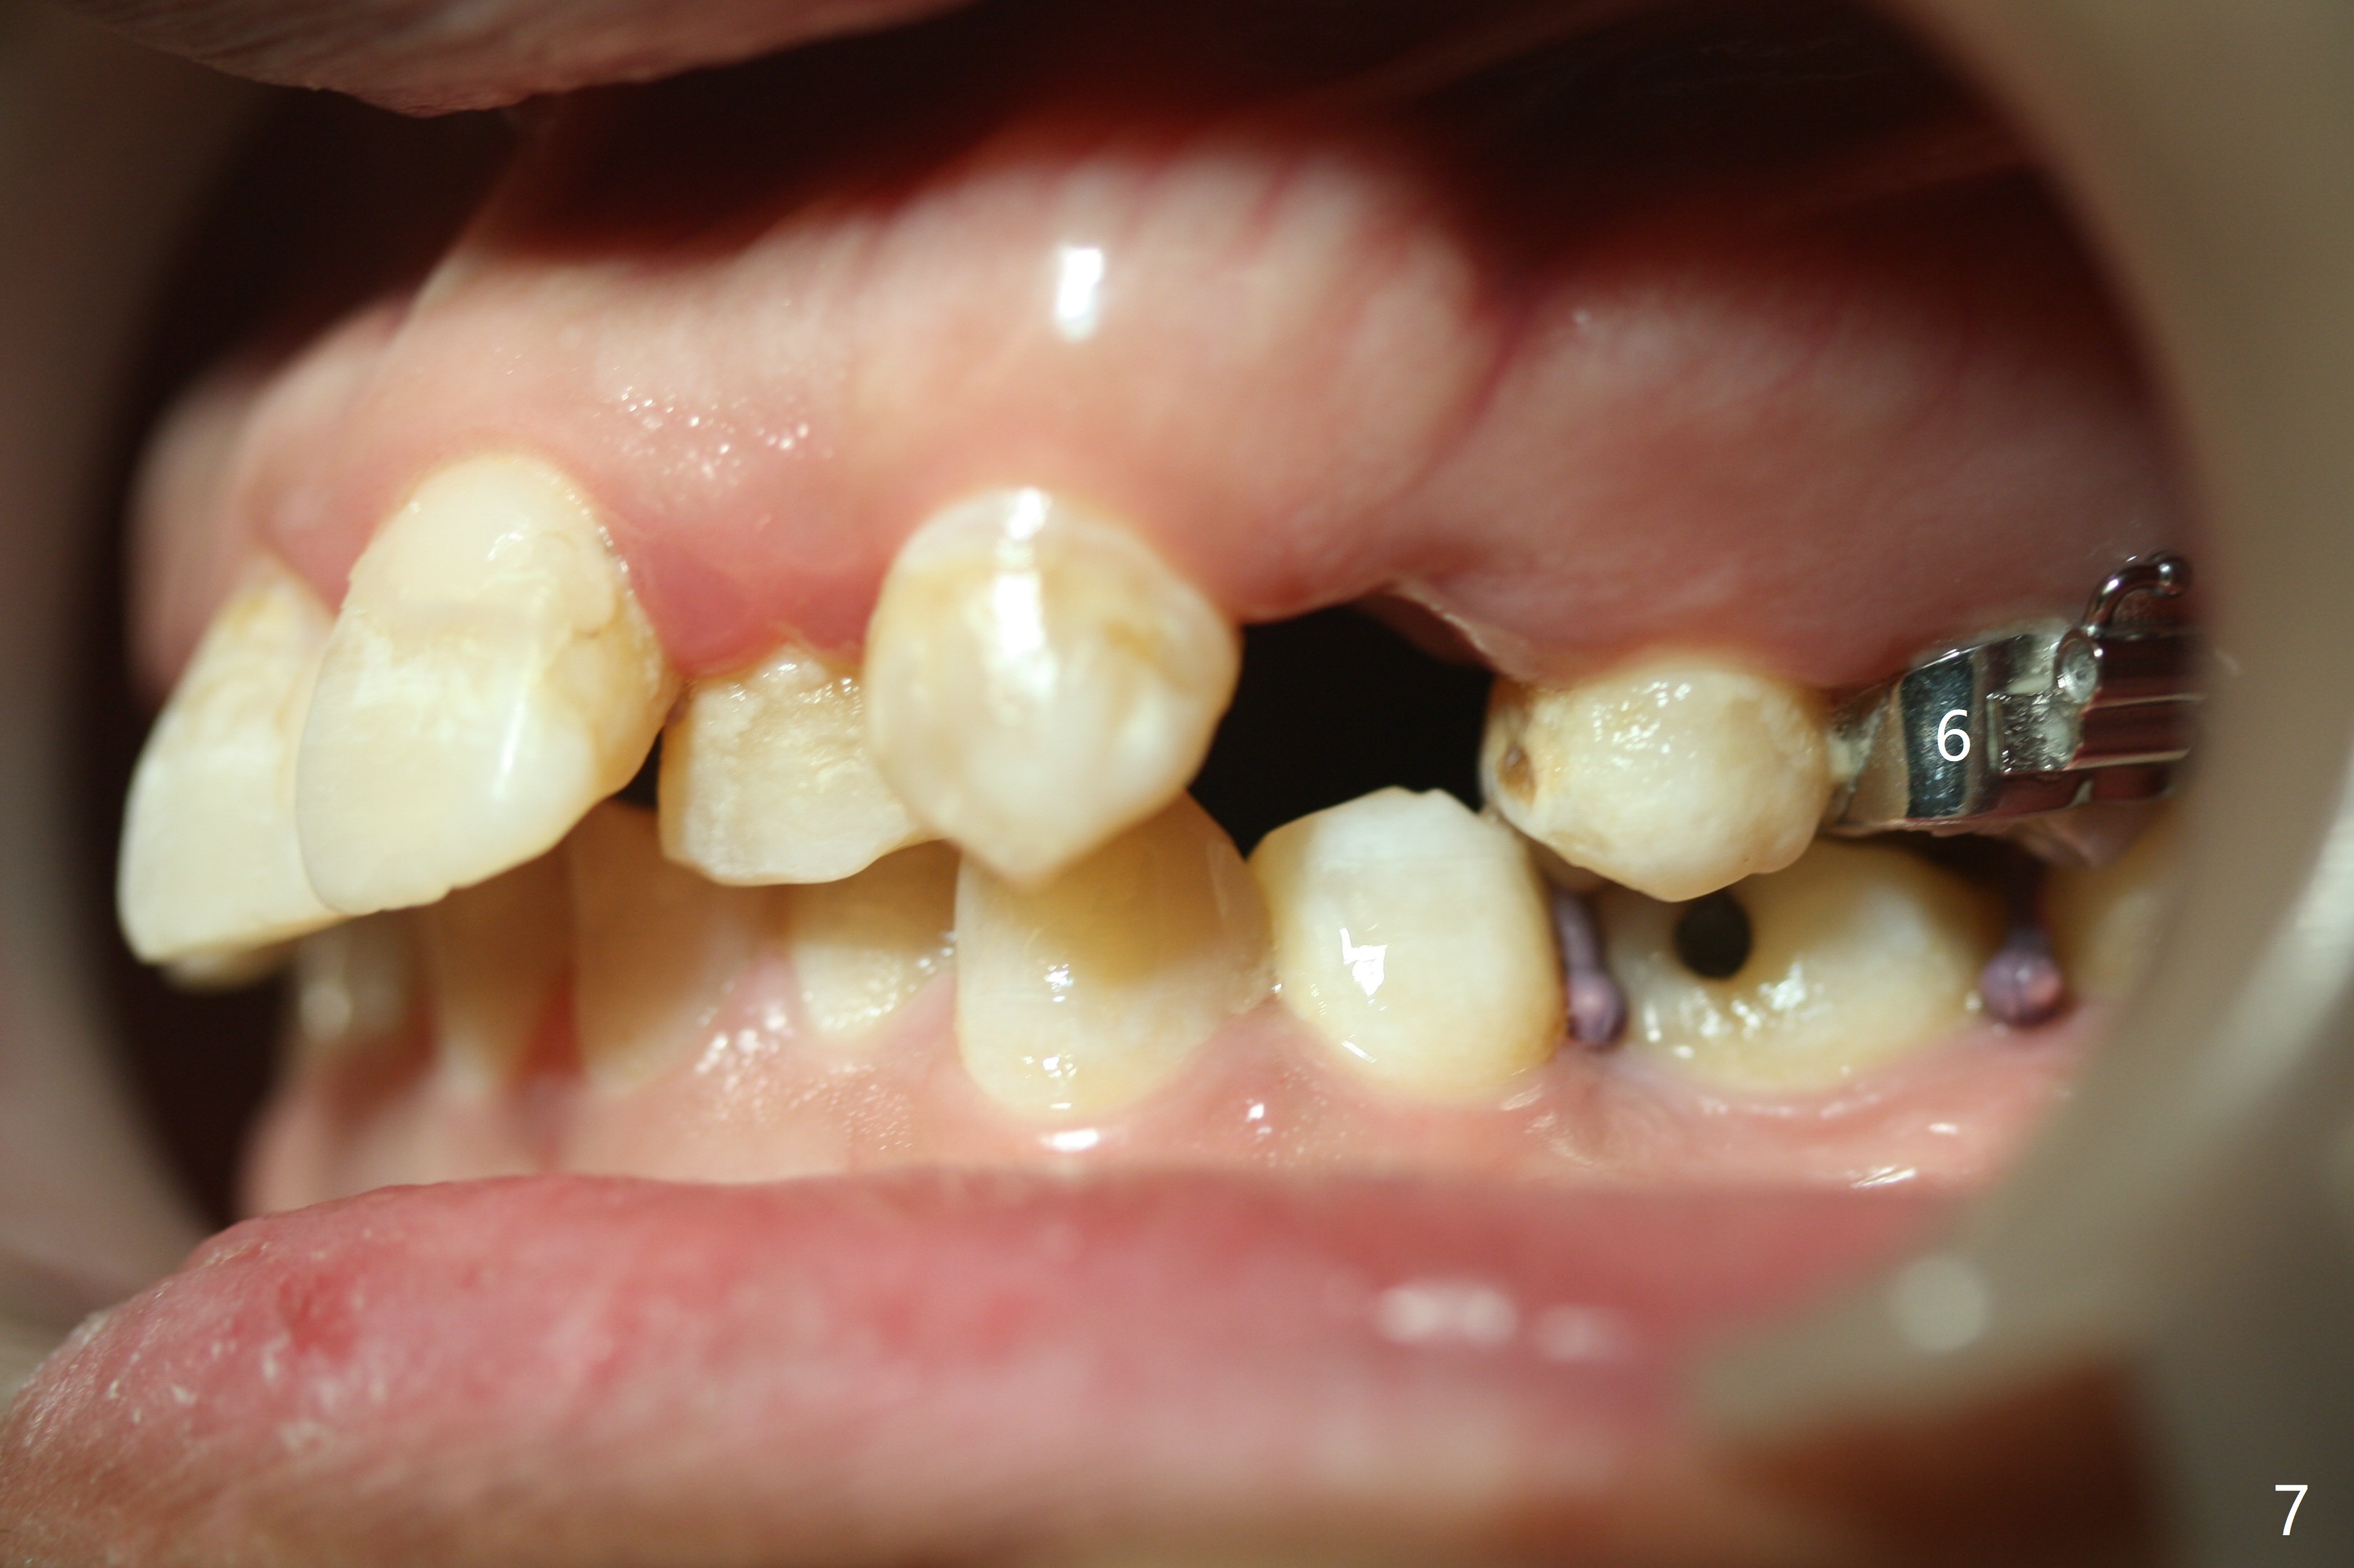

Severe crowding (Fig.1-7) appears to be alleviated especially 2 months after UR5 extraction. Diastemata seem to form mesial and distal to UR2 (Fig.8). Because of severe wear at UR3 (Fig.6), there is no bracket placement differential around it (Fig.8 (14 niti wire)). Lower bands and brackets are placed a week later (Fig.9-11). Because of tight space between LR4 and the opposing tooth (Fig.10), band adhesive is applied to L7 occlusal surface to open the bite (Fig.9). There is an abrupt kink of 12 niti wire between LL4 and 6 (Fig.11). The latter does not improve much in a month; the wires remain the same (Fig.12). For LL2, LR4 has been retracted for ~ 1 month (Fig.13). There is mild tension when 18 ss wire is inserted between LL4 and 6 five point five months post banding (Fig.14). UR4 has been distalized for a month using buccal power chains x3 resulting in rotation; to counter the rotation, a lingual button is placed with power chain x3 lingual and x2 buccal (Fig.15). With space gaining, it is time to finish definitive filling (Fig.16 *). Next visit check midlines, overjet, interdigitation, and molar classification. R4s distalize, but associate with rotation because of power chains buccal and lingual 8 months post banding (Fig.17,18). With the use of the same wires, power chains are applied lingual to continue distalization and rotation correction (Fig.20,21). Lingual buttons are placed at L2s buccalization (Fig.19) and mesialization (Fig.22,23). It appears that space should be created distal to LR3. That is that the lower anterior teeth should be shifted to the right, although it may be not appropriate for the midline.